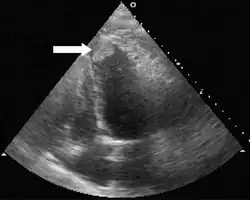

- Vorhofthrombus: bei Vorhofflimmern kann es zur Thrombenbildung im Vorhof (insbesondere im Herzohr) kommen.